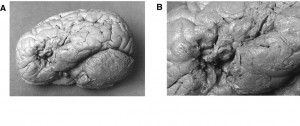

Quando ancora la neurologia muoveva i primi passi, per esempio, nel 1800 il neurologo Paul Broca ebbe in cura un paziente afasico (Leborgne, detto “Tan-Tan”): non riusciva a parlare perché aveva leso un’area del cervello – poi chiamata in suo onore area di Broca, nell’emisfero sinistro – che controlla il linguaggio. Eppure Leborgne riusciva a dire “Sacro nome di Dio!” quando si arrabbiava. Perché – si è scoperto poi – le parolacce sono controllate dall’altro emisfero, il destro. Dunque, grazie alla neurologia si è scoperto che le parolacce possono sopravvivere all’afasia; e non sono un “sintomo”, bensì uno dei pochi campi di libera espressione dei malati che hanno perso l’uso di tutte le altre le parole.

Detto per inciso, proprio la recente conoscenza della specializzazione delle aree cerebrali spiega altri fatti sorprendenti. Per esempio il motivo per cui i pazienti che hanno avuto lesioni cerebrali per incidenti, tumori, ictus, possono perdere la parola (diventare cioè afasici) ma non le parolacce: in questi casi,la lesione cerebrale è nell’emisfero sinistro,e non nel destro (quello che controlla le parolacce).